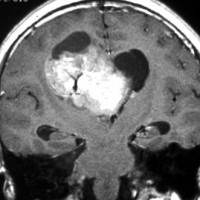

無症状で偶然発見された38歳女性の症例

central neurocytomaが透明中隔 septum pellucidum から発生していることがよくわかる症例です。症状はありませんでしたが,この腫瘍がこのままのサイズで留まることはあり得ないので手術摘出を勧めました。これ以上大きくなると手術にしても放射線治療にしてもリスクが大きくなりすぎます。脳弓にくっつくので脳弓損傷を避けるのが手術のポイントです。脳室壁にくっつくのですが剥がしていけば取れますが,大きな上衣下静脈 large subependymal vein の損傷には注意を払います。

手術後の画像です。脳神経外科の先生は手術根 surgical track に注目して下さい,左頭頂葉皮質切開 transcortical approachで手術を行っています。このルートでは全く手術後の神経脱落症状が出ませんでした。central neurocytomaの手術方法は,上記に加えて前頭葉皮質切開でまっすぐ前角に入る方法と経脳梁法 transcallosal approachがあります。経脳梁法は限られた小さめの腫瘍にしか応用できません。anterior callosal approach以外ではdisconnection syndromeが出るからです。central neurocytomaは脳室の壁にベトベトくっつくし,anterior callosal approachでは脳室壁の観察はかなり限られるからです。大きなものでは必ず経皮質法を選択して下さい。